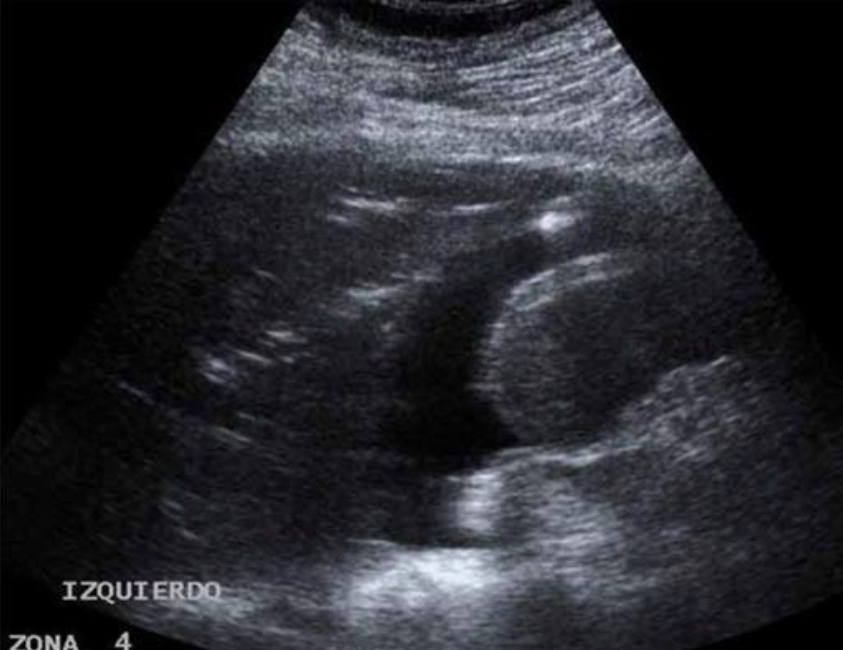

胸腔积液

为脏层与壁层胸膜之间的无回声暗区,合并压缩性肺不张时,可出现「海蜇征」或「舌头征」